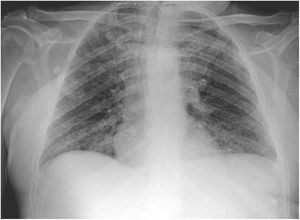

The second patient was a 59-year-old man with vascular risk factors and substance use disorder. He was admitted due to a 3-day history of high fever, cough, and general discomfort. A blood analysis showed leukocytosis (20400cells/mm3) with neutrophilia (87%), lymphocytopaenia (900cells/mm3), and high levels of d-dimer (1500ng/mL), creatinine (2.8mg/dL), sodium (157mmol/L), LDH (761IU/L), CPK (780IU/L), transaminases, C-reactive protein (180mg/L), and ferritin (2900ng/mL), as well as hypoxaemia with hypocapnia. A chest radiography showed interstitial infiltrate in the lung base bilaterally (Fig. 2). We conducted a microbiology study similar to that performed in the first patient, and the PCR test for SARS-CoV-2 yielded positive results.